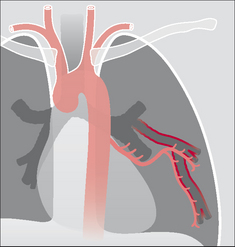

Figure 30.3 Haemoptysis due to bronchiectasis. The chronic inflammation can cause localised proliferation of the bronchial arteries; these vessels may become friable and cause a mild haemoptysis. Sometimes the bronchial arteries are actually eroded by the inflammatory process and a massive haemoptysis results.